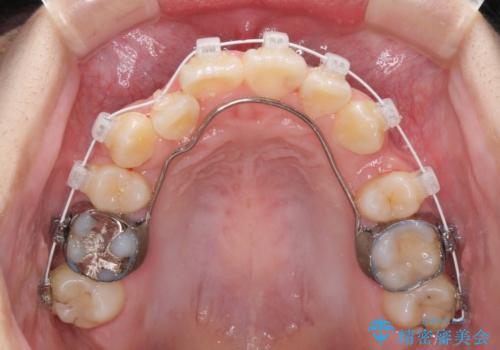

デコボコが強いため小臼歯4本を抜歯し、上顎正中を左側に移動させるために補助装置を使用して、ワイヤー装置にて矯正治療を行うこととしました。

正中位置の改善に時間がかかることが予想され、2年半を治療期間の目標としておりましたが、20歳と年齢が若いこともあり、2年2ヶ月で治療を終えることができました。